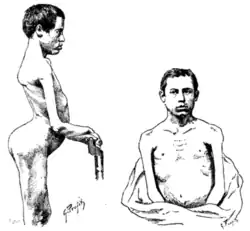

| 1861 | Person with muscular dystrophy depicted by Duchenne. Based on the muscles involved, this person could have had FSHD. |

| 1884 | Landouzy and Dejerine describe a form of childhood progressive muscle atrophy with characteristic involvement of facial muscles distinct from pseudohypertrophic (Duchenne's MD) and spinal muscle atrophy in adults.[128]

Two brothers with FSHD followed by Landouzy and Dejerine Photograph of one brother at age 21. The right scapula is protracted, downwardly rotated, and laterally displaced. Drawing of another brother at age 17. Visible is lumbar hyperlordosis. The upper arm and pectoral muscles appear atrophied. |